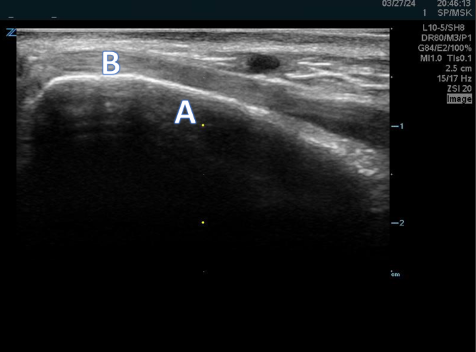

A 57-year-old male presents after a fall onto his left side. An ultrasound is performed along the 7th rib where he is point tender.

Read More...